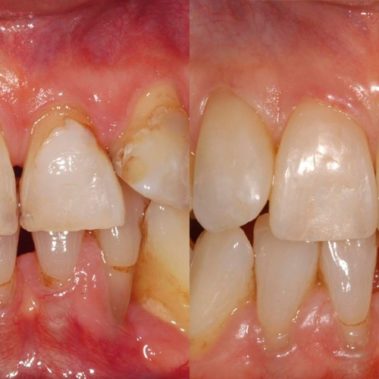

Unser hochqualifiziertes Praxisteam aus Zahnärzten und Mitarbeiterinnen steht Ihnen mit Achtsamkeit, Vertrauen und Professionalität in Kemnath zur Verfügung.